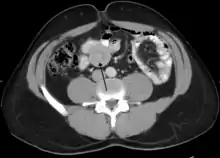

| An intussusception as seen on CT | |

An intussusception is often suspected based on history and physical exam, including observation of Dance's sign. A digital rectal examination is particularly helpful in children, as part of the intussusceptum may be felt by the finger. A definite diagnosis often requires confirmation by diagnostic imaging modalities. Ultrasound is the imaging modality of choice for diagnosis and exclusion of intussusception, due to its high accuracy and lack of radiation. The appearance of target sign (also called "doughnut sign" on a sonograph, usually around 3 cm in diameter, confirms the diagnosis. The image seen on transverse sonography or computed tomography is that of a doughnut shape, created by the hyperechoic central core of bowel and mesentery surrounded by the hypoechoic outer edematous bowel.[10] In longitudinal imaging, intussusception resembles a sandwich.[10] It is also called "pseudokidney" sign because hyperechoic tubular centre is covered by a hypoechoic rim producing a kidney-like appearance.[11]